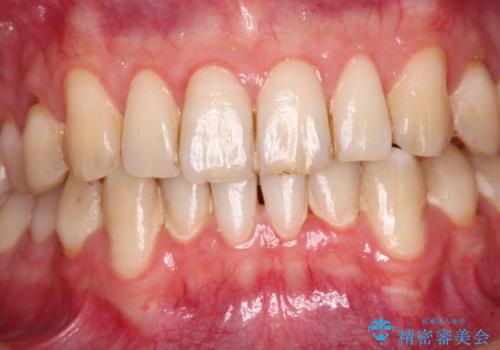

歯肉移植により根面被覆が達成されるとともに、歯肉が厚みを増したことで、今後の歯肉退縮リスクを軽減させることができました。